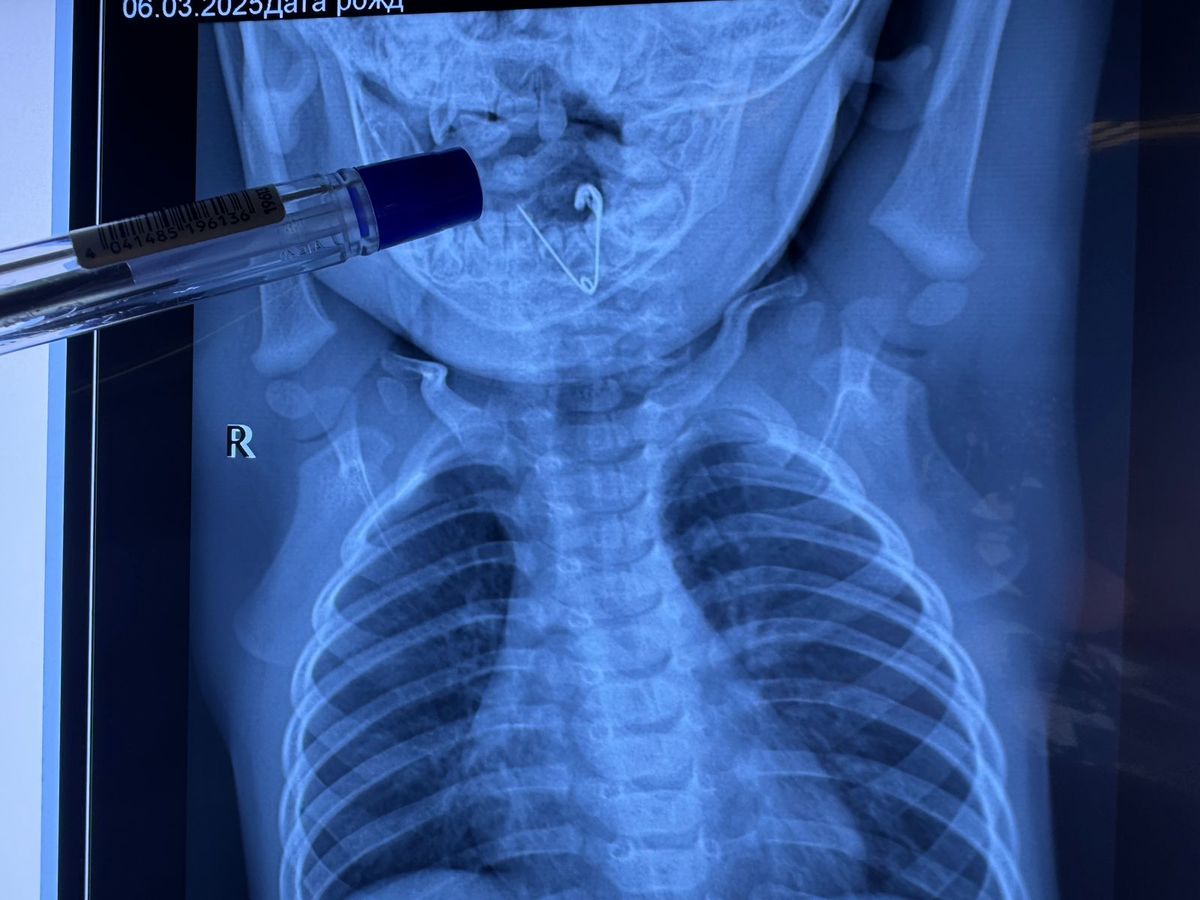

Врачи Краевой детской клинической больницы № 1 во Владивостоке извлекли из пищевода семимесячного мальчика открытую булавку. Опасный предмет был прикреплён к одеяльцу, с которого ребёнок его снял и отправил в рот.